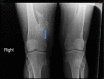

Figure 2. X-ray of both knee joints

Multiple exostoses involving bilateral distal femur, proximal tibia, and fibula, the largest is arising from the right distal femur (blue arrow).